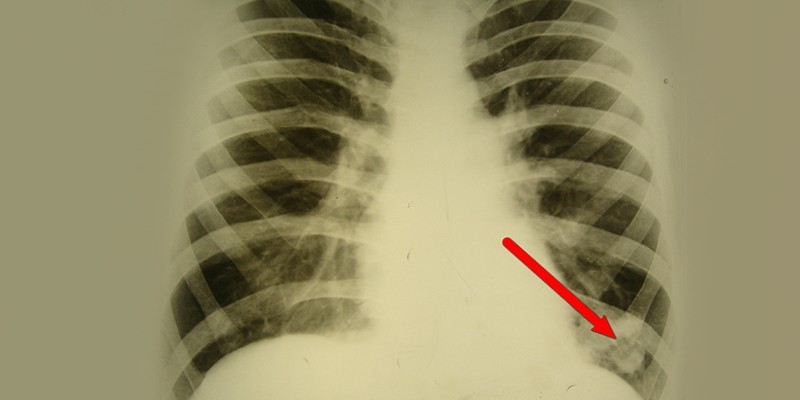

Хронический абсцесс легкого может возникнуть вследствие осложнения инфекции или туберкулеза. Врачи отмечают, что основными симптомами этого заболевания являются кашель с гнойным отхаркиванием, боль в груди, повышенная температура тела и общая слабость. Для диагностики абсцесса легкого необходимо провести рентгенологическое исследование, компьютерную томографию и бактериологические анализы мокроты.

Хронический абсцесс легкого – серьезное заболевание, вызванное образованием гнойного полости в легочной ткани. Основные причины его возникновения связаны с инфекцией, чаще всего вызванной бактериями. Симптомы включают кашель с гнойной мокротой, боль в груди, лихорадку. Диагностика проводится с помощью рентгена, компьютерной томографии и бактериологических исследований. Лечение включает антибиотики, дренирование абсцесса и в некоторых случаях хирургическое вмешательство. Важно обратиться к врачу при первых признаках заболевания, чтобы избежать осложнений.

Хронический абсцесс нужно дифференцировать от туберкулеза, актиномикоза, полостной формы периферического рака легкого. Основная диагностика проводится по тем же принципам, что и при подозрении на острую форму гнойного воспаления. У большинства пациентов с хроническим абсцессом в анамнезе обнаруживается перенесенное ранее гнойно-деструктивное воспаление. Диагностика включает следующие исследования:

- рентгенологическое исследование;

- компьютерная томография легких;

Для постановки диагноза пациенту предложат сдать анализ крови и мочи, проведут анализ выделяемой мокроты и бактериоскопию с бакпосевом, что позволит точно выявить возбудителя и определить его чувствительность к медицинским препаратам. Также проводится рентгенография легких, КТ и МРТ легких и ряд других исследований.